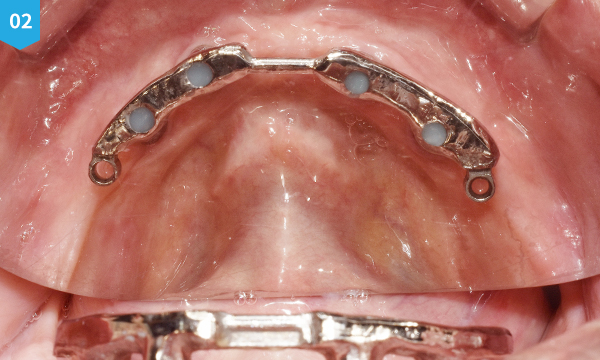

Bar type 임플란트 틀니는 윗턱에는 임플란트를 6개, 아래턱에는 4개를 심어 금속으로 된 바를 입안에 고정시킨 후, 그 Bar에 틀니를 결찰 하는 고정력이 우수하며 통증이 없는 틀니입니다.

불편한 착용감과 고정력이 약한 기존에 틀니와는 다르게 잇몸 안에 임플란트를 심은 후 특수 제작한 금속 바에 틀니를 창작하여 고정력이 매우 우수합니다. 또한, 바(bar)에 장착된 틀니는 통증이 없으며, 인중이 많이 주저 않아 나이 들어 보이시는 분들에게 심미적인 개선 효과도 기대할 수 있습니다.

바(bar) 타입 임플란트 틀니는 치아와 잇몸 뼈가 너무 없어, 임플란트가 불가능한 분들에게도 시술이 가능합니다. 바 타입 틀니는 섬세함을 필요하는 고난도의 시술이기 때문에, 의료진의 노하우가 매우 중요합니다. 일등플란트치과는 미국 치과 임플란트 학회 (AAID)의 인정의를 비롯, 다년간의 풍부함 경험을 바탕으로 정밀하게 시술하고 있으며, 원내 기공실을 통해 개인의 구강 상태에 꼭 맞는 바(bar)를 직접 제작하여, 보다 만족스럽고 편안한 착용을 위해 노력하고 있습니다.

위턱과 아래턱에 임플란트를 심은 후 환자 구강 상태에 맞춰 원내 기공소에서 직접 제작한 바를 입안에 고정시켜 통증 없이 편한 착용감에 틀니를 만족스럽게 사용하실 수 있도록 시술합니다.